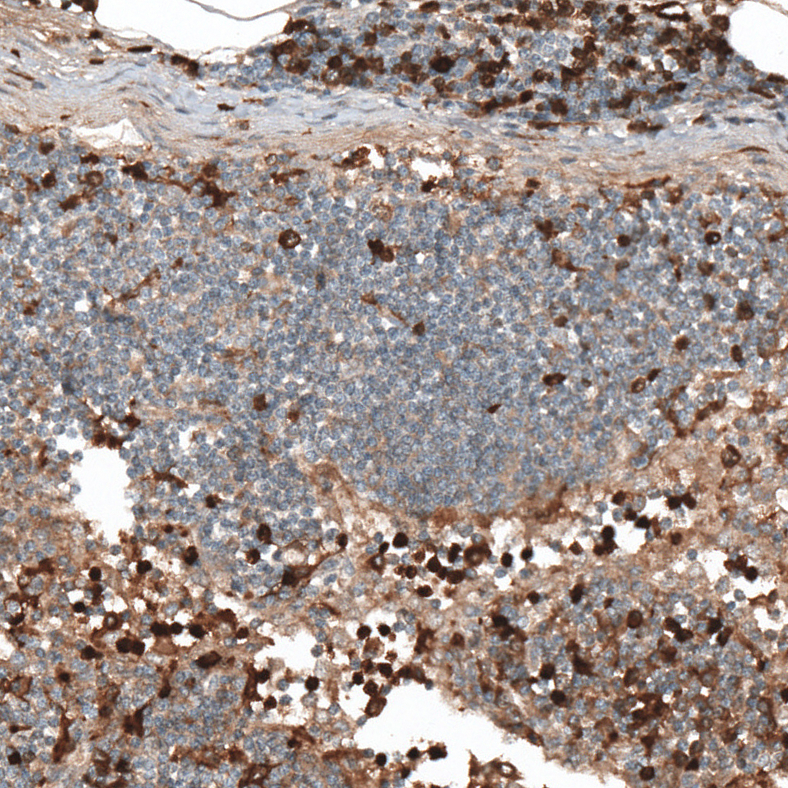

Immunohistochemical staining of human lymph node shows moderate to strong nuclear positivity in lymphoid cells.